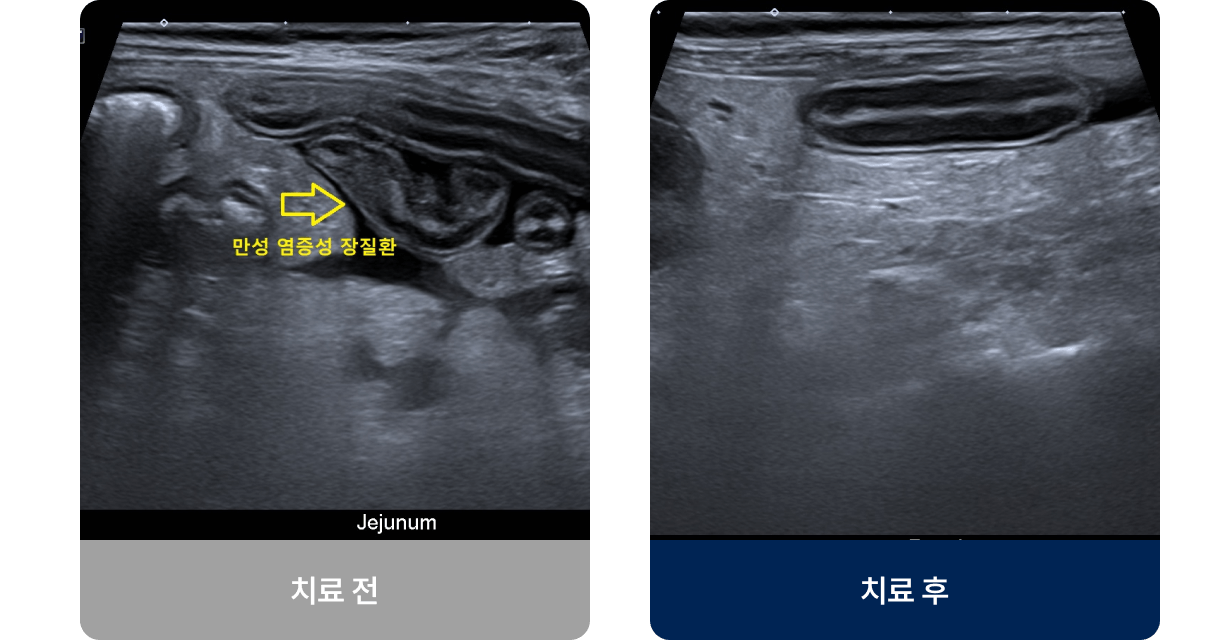

면역 반응 이상이나 음식 알레르기, 장내 세균 불균형 등으로 인해 소장과 대장에 만성 염증이 생기는 질환입니다. 주로 성견이나 고양이에게 많이 나타나며, 설사와 구토가 반복되고, 변의 상태가 일정하지 않거나 체중이 줄어드는 증상이 나타납니다. 진행되면 영양 흡수 장애와 만성 체력 저하로 이어질 수 있습니다.